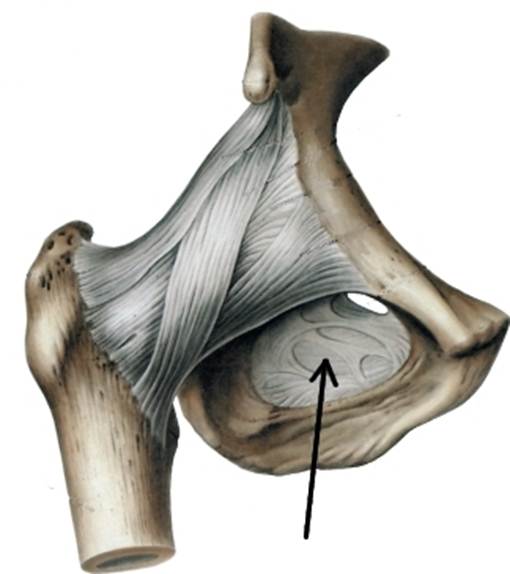

Структура и анатомия синдесмоза: научные иллюстрации